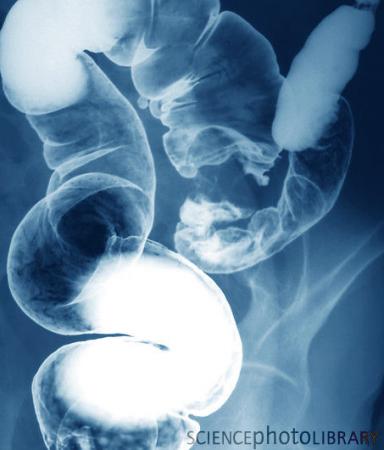

大肠癌

大肠癌(Colorectal Cancer)为结肠癌和直肠癌的总称,是胃肠道最常见的恶性肿瘤之一,仅次于胃癌、食管癌。约半数患者接受传统切除手术后癌细胞会转移或扩散,而一旦出现转移或扩散,5年存活率只有8%。(推荐阅读:经常久坐提高罹患大肠癌风险 )